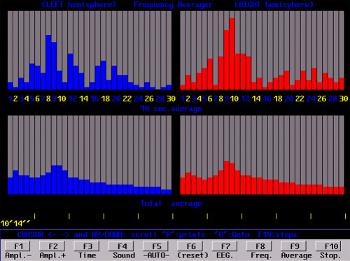

Outra maneira de ver os resultados é através do tempo e não pela média. As imagens abaixo são partidas ao meio por uma linha vertical branca: o hemisfério esquerdo está à esquerda de cada imagem e o direito à direita.

A escala vertical mede o tempo em segundos. A escala horizontal mede a frequência e a intensidade das ondas cerebrais. Você poderá ver, como no exemplo acima, a diferença no equilíbrio e na predominância das ondas Alpha.

Mostra a potência de cada frequência de 1 a 30 Hz. Esta é a tela que apresenta mais claramente o total do equilíbrio entre os hemisférios e a frequência dominante, tanto segundo por segundo como numa média do total do teste. Este exemplo é a média de atividade durante uma sessão de estimulação óptico-

Média móvel de 10 segundos

Mostra a frequência média, intensidade e equilíbrio esquerdo/direito dos últimos 10 segundos. A parte inferior da imagem mostra a mesma informação como um acumulado total do teste.